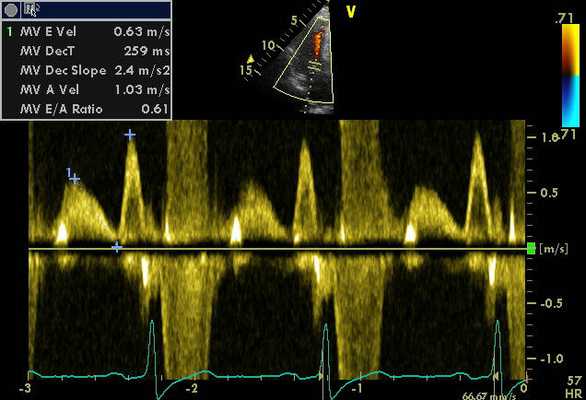

Эхокардиография с доплеровским анализом

Для оценки турбулентности системы кровообращения, а также скорости тока крови потребуется эхокардиография с доплеровским анализом. На сегодняшний день метод считается наиболее востребованным исследованием в кардиологии, особенно для диагностирования сердечных патологий в детском возрасте. Какие существуют показания к проведению анализа? Какими преимуществами обладает исследование и как правильно к нему подготовиться?

Основная характеристика исследования

Эхокардиографию с доплеровским анализом считают наиболее эффективной методикой для определения расположения и работы различных сердечных структур в режиме реального времени.

Допплеровский принцип широко применяют в медицине для определения направленности кровотока в сосудах и структурах сердца

Основа метода заключается в вычислении соотношения скорости передвижения объекта по отношению к видоизмененной частоте отражаемого сигнала. При соприкосновении ультразвуковых волн с перемещающимися кровяными тельцами наблюдается преобразование частот, значимость которой является доплеровским сдвигом. Поскольку частота воспроизводства ультразвуковой волны постоянна, то изменение ее частоты указывает на направление и скорость тока крови. Как правило, он воссоздается эхо-прибором в виде слышимого сигнала, который доступен для восприятия человека.

Используемые виды допплерографии

Современная ультразвуковая аппаратура позволяет осуществлять диагностику с допплерометрией в трех основных режимах:

Метод цветного картирования (ЦДК) - это очень эффективное исследование, позволяющие произвести оценку состояния не только сосудов, но и выявить локализацию тромбов, атеросклеротических бляшек, а также аневризму аорты. Интерпретация данных помогает определить специалисту характер новообразования и темп его развития.

Методика спектральной допплерографии объединяет в себе постоянный и импульсно-волновой режимы

На сегодняшний день наиболее широко применяемым исследованием при помощи допплера является тканевая методика. Данный метод оптимизирован для изучения не только направления кровотока, но и визуализации движений сердечных тканей. В ходе допплеровского анализа происходит окрашивание миокарда в различные цвета в соответствии со скоростью и направленностью кровяного потока. Технику применяют для выявления локализованных изменений в сократительной функции миокарда. Данные, получаемые в ходе анализа, регистрируются в виде графика, отображающего зависимость скорости от времени.

Оценка результатов

Данные, полученные в ходе процедуры, являются важным диагностическим критерием, поэтому их расшифровкой должен заниматься высококвалифицированный кардиолог. В первую очередь специалист проводит оценку сократительной способности миокарда, а затем определяет параметры, функциональное состояние левого и правого желудочков.

Параметры работы сердца и движения кровотока в норме